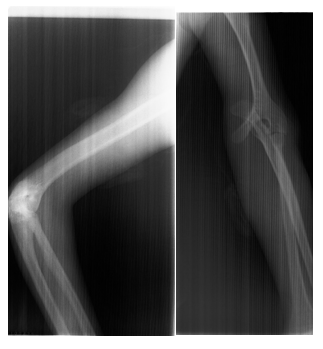

Radiographic limbs show bony ankylosis of the elbow joint, with associated hypoplasia of the ulna and proximal radius, leading to elbow flexion deformity on the left side (Figure 5). Chest x-rays show no apparent abnormalities: normal lung fields, cardiac silhouette, and bony structures (Figure 6) PA skull view show hypoplastic maxilla, prominent antigoinial notch and deviation of mandible to left side (Figure 7 &Table 1).

Figure 5 Radiograph of the left upper limb showing bony ankylosis of the elbow joint with hypoplasia of the ulna and proximal radius, resulting in an elbow flexion deformity.